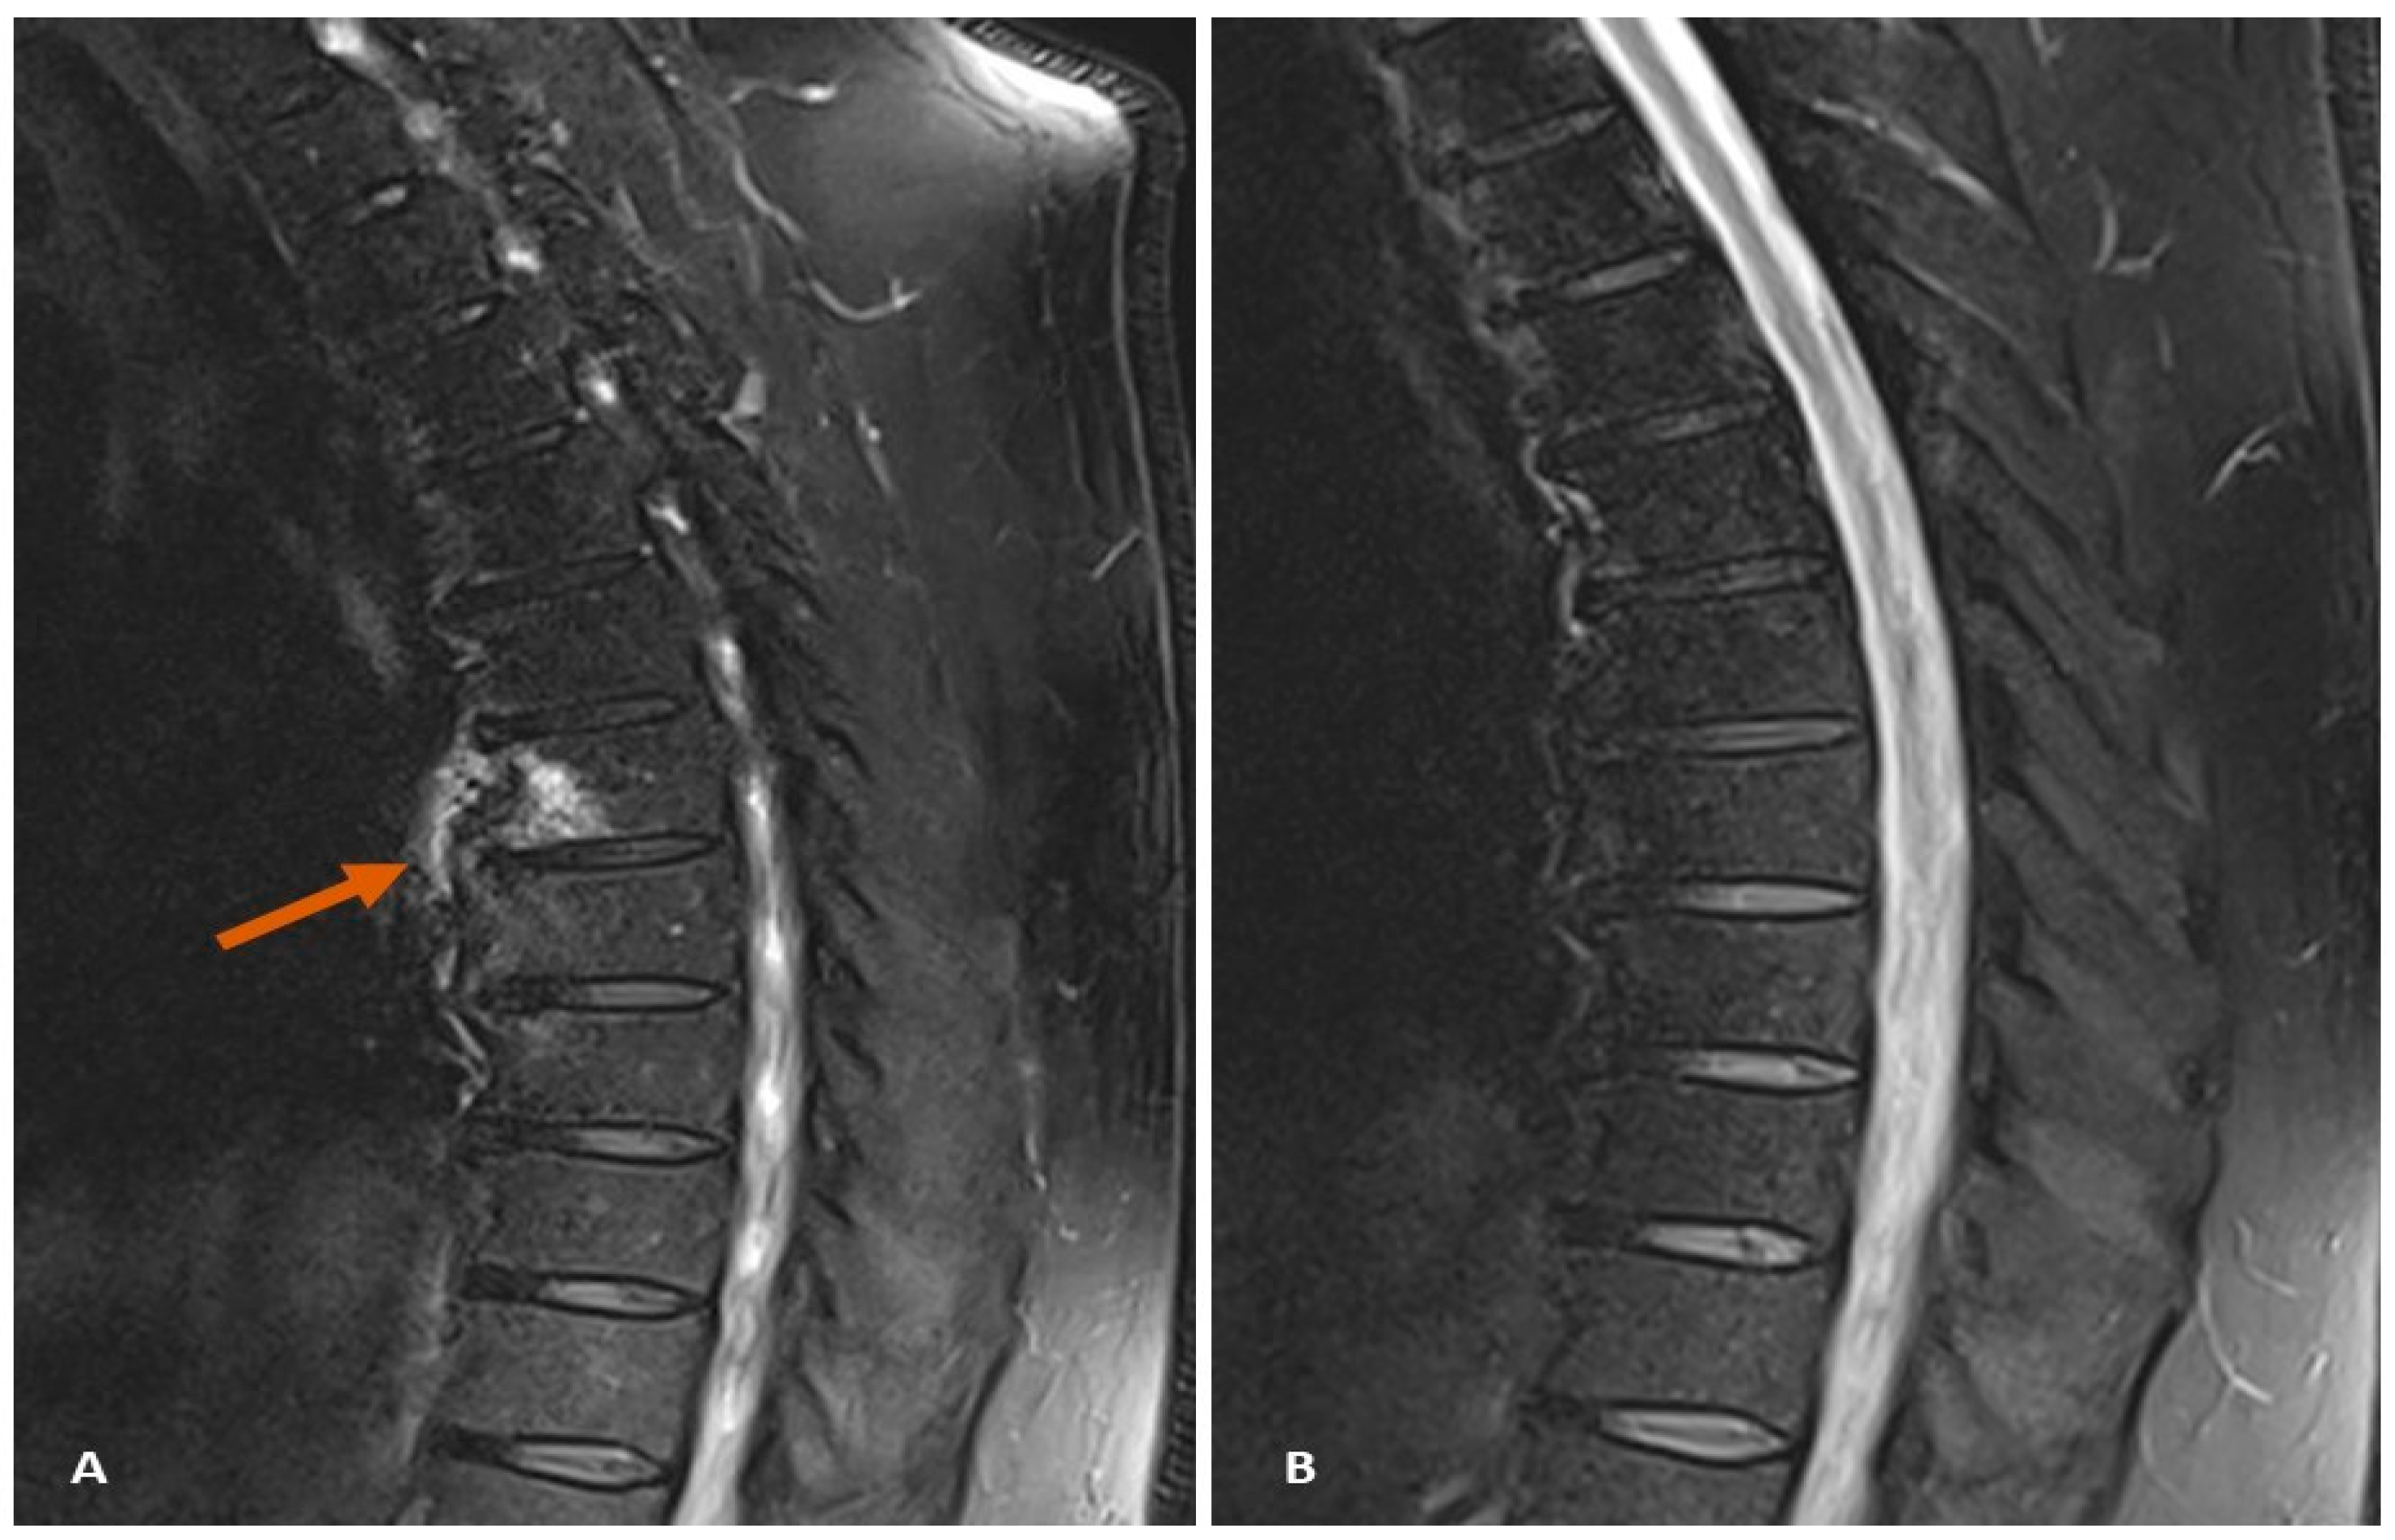

7.2. Case Study 2